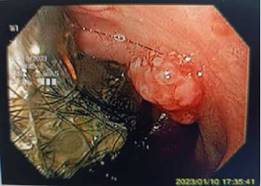

Figura 2: Endoscopia alta, se evidencia una lesión sobreelevada a nivel de duodeno y el tricobezoar.